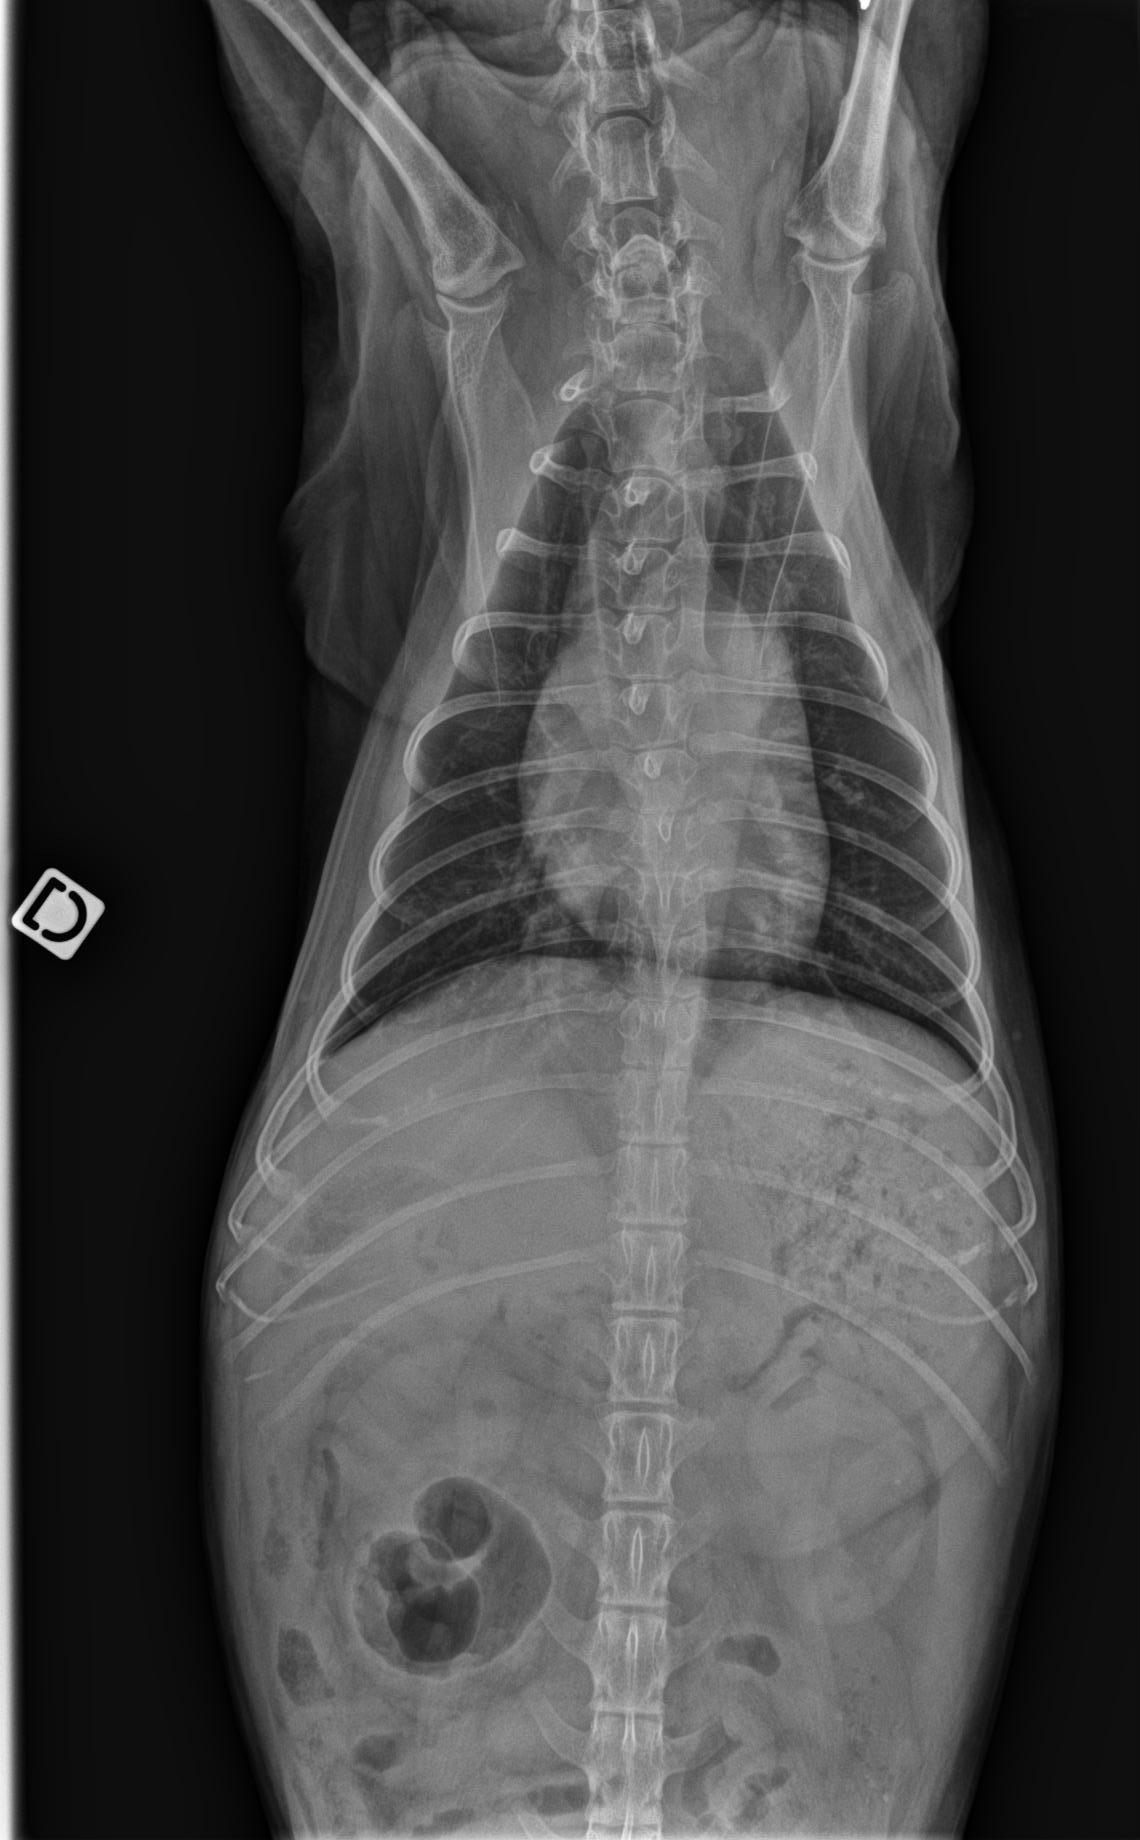

Geste technique : Mesure échographique du LA/Ao (rapport oreillette gauche/aorte)

- Connaître les principaux examens à considérer chez un chien présenté en dyspnée aigue

- Connaître les limites de l’examen échographique pour l’exploration d’une dyspnée aigue chez le chien

- Connaître les limites de l’examen sanguin (mesure BNP) pour l’exploration d’une dyspnée aigue chez le chien